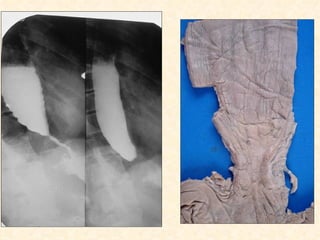

Esofagite cáustica

 Ácidos

 Álcalis

 Outras substâncias corrosivas

 Evolução

    Necrose e dissolução

    Inflamação

    Estenose

 (radioterapia)

• 43.

Esofagite cáustica  Ácidos Álcalis  Outras substâncias corrosivas  Evolução  Necrose e dissolução  Inflamação  Estenose  (radioterapia)